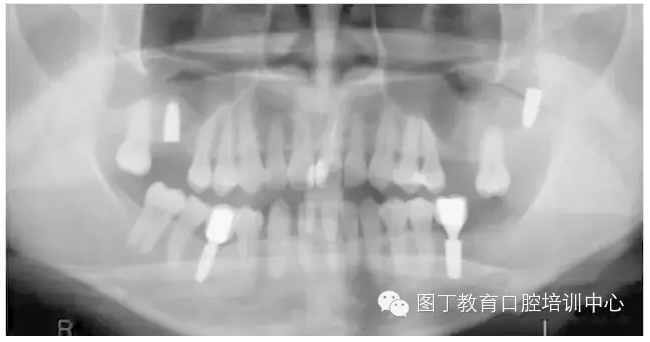

病例9 種植體進(jìn)入額竇腔內(nèi)(圖11)

圖11

④種植體植入上頜竇或其他竇腔的情況較少見(jiàn),但可能在患者為Ⅳ類骨或骨量少時(shí)發(fā)生,5~6mm骨量時(shí)也可能發(fā)生(如圖11所示)。